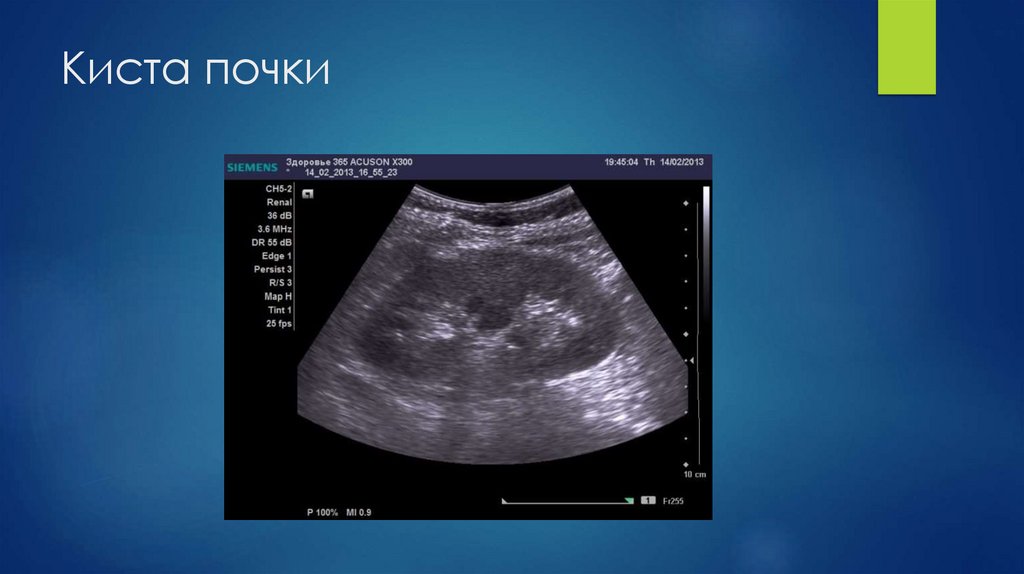

13. Киста почки

14. Киста почки